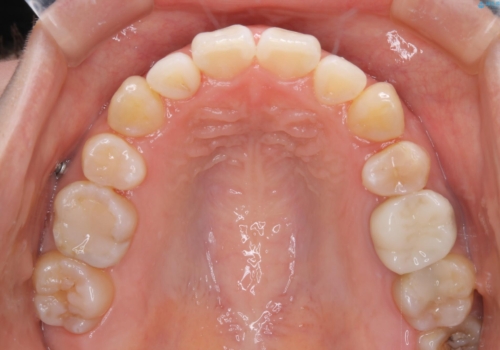

- 全体的に着色が付いているのが気になるとのことで来院されました。

PMTC60分コースを行いました。

着色がかなり頑固なため、エアフローも使い着色を除去していきました。

下の前歯にはかなり多くの歯石が付いており、デンタルフロスでもう少し防げるため、使用法や頻度を確認しました。